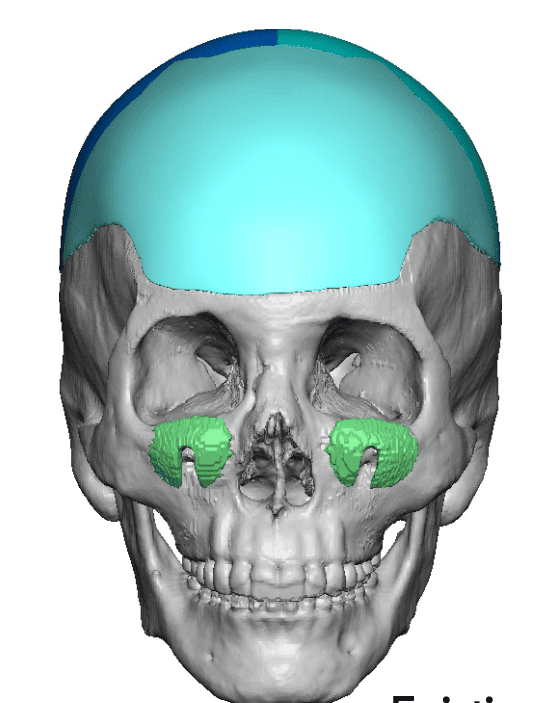

Patient 84

Desire for change of head shape from front view form an inverted V shape to a rounder and wider head shape.

Placement of custom extended forehead-temporal implants through incisions in the crease behind the ear. (he had a prior back of head skull implant which is green in the implant designs and which the head widening implants partially covered it)

Desire for change of head shape from front view form an inverted V shape to a rounder and wider head shape.

Placement of custom extended forehead-temporal implants through incisions in the crease behind the ear. (he had a prior back of head skull implant which is green in the implant designs and which the head widening implants partially covered it)